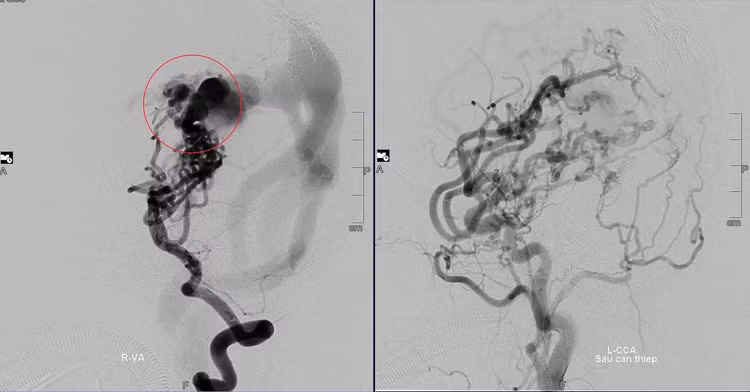

Hình ảnh mạch máu não của bệnh nhân trước và sau khi được các bác sĩ can thiệp. Ảnh tienphong.vn

Theo BS-CKI Dương Hoàng Linh, đơn vị can thiệp DSA, Bệnh viện S.I.S Cần Thơ, để tối ưu hóa việc điều trị cho bệnh nhi, các bác sĩ đã xây dựng chiến lược dài hạn gồm nhiều lần can thiệp để giảm dần lưu lượng máu qua khối dị dạng, từ đó giảm nguy cơ vỡ mạch máu.

“Trong 10 năm qua, bé D. đã trải qua 8 lần can thiệp mạch não. Mỗi lần là một cuộc chiến căng thẳng giữa sự sống và cái chết. Việc can thiệp, điều trị cho trẻ đòi hỏi sự phối hợp chính xác đến tuyệt đối của đội ngũ y bác sĩ và lòng tin từ gia đình”, bác sĩ Linh cho biết.